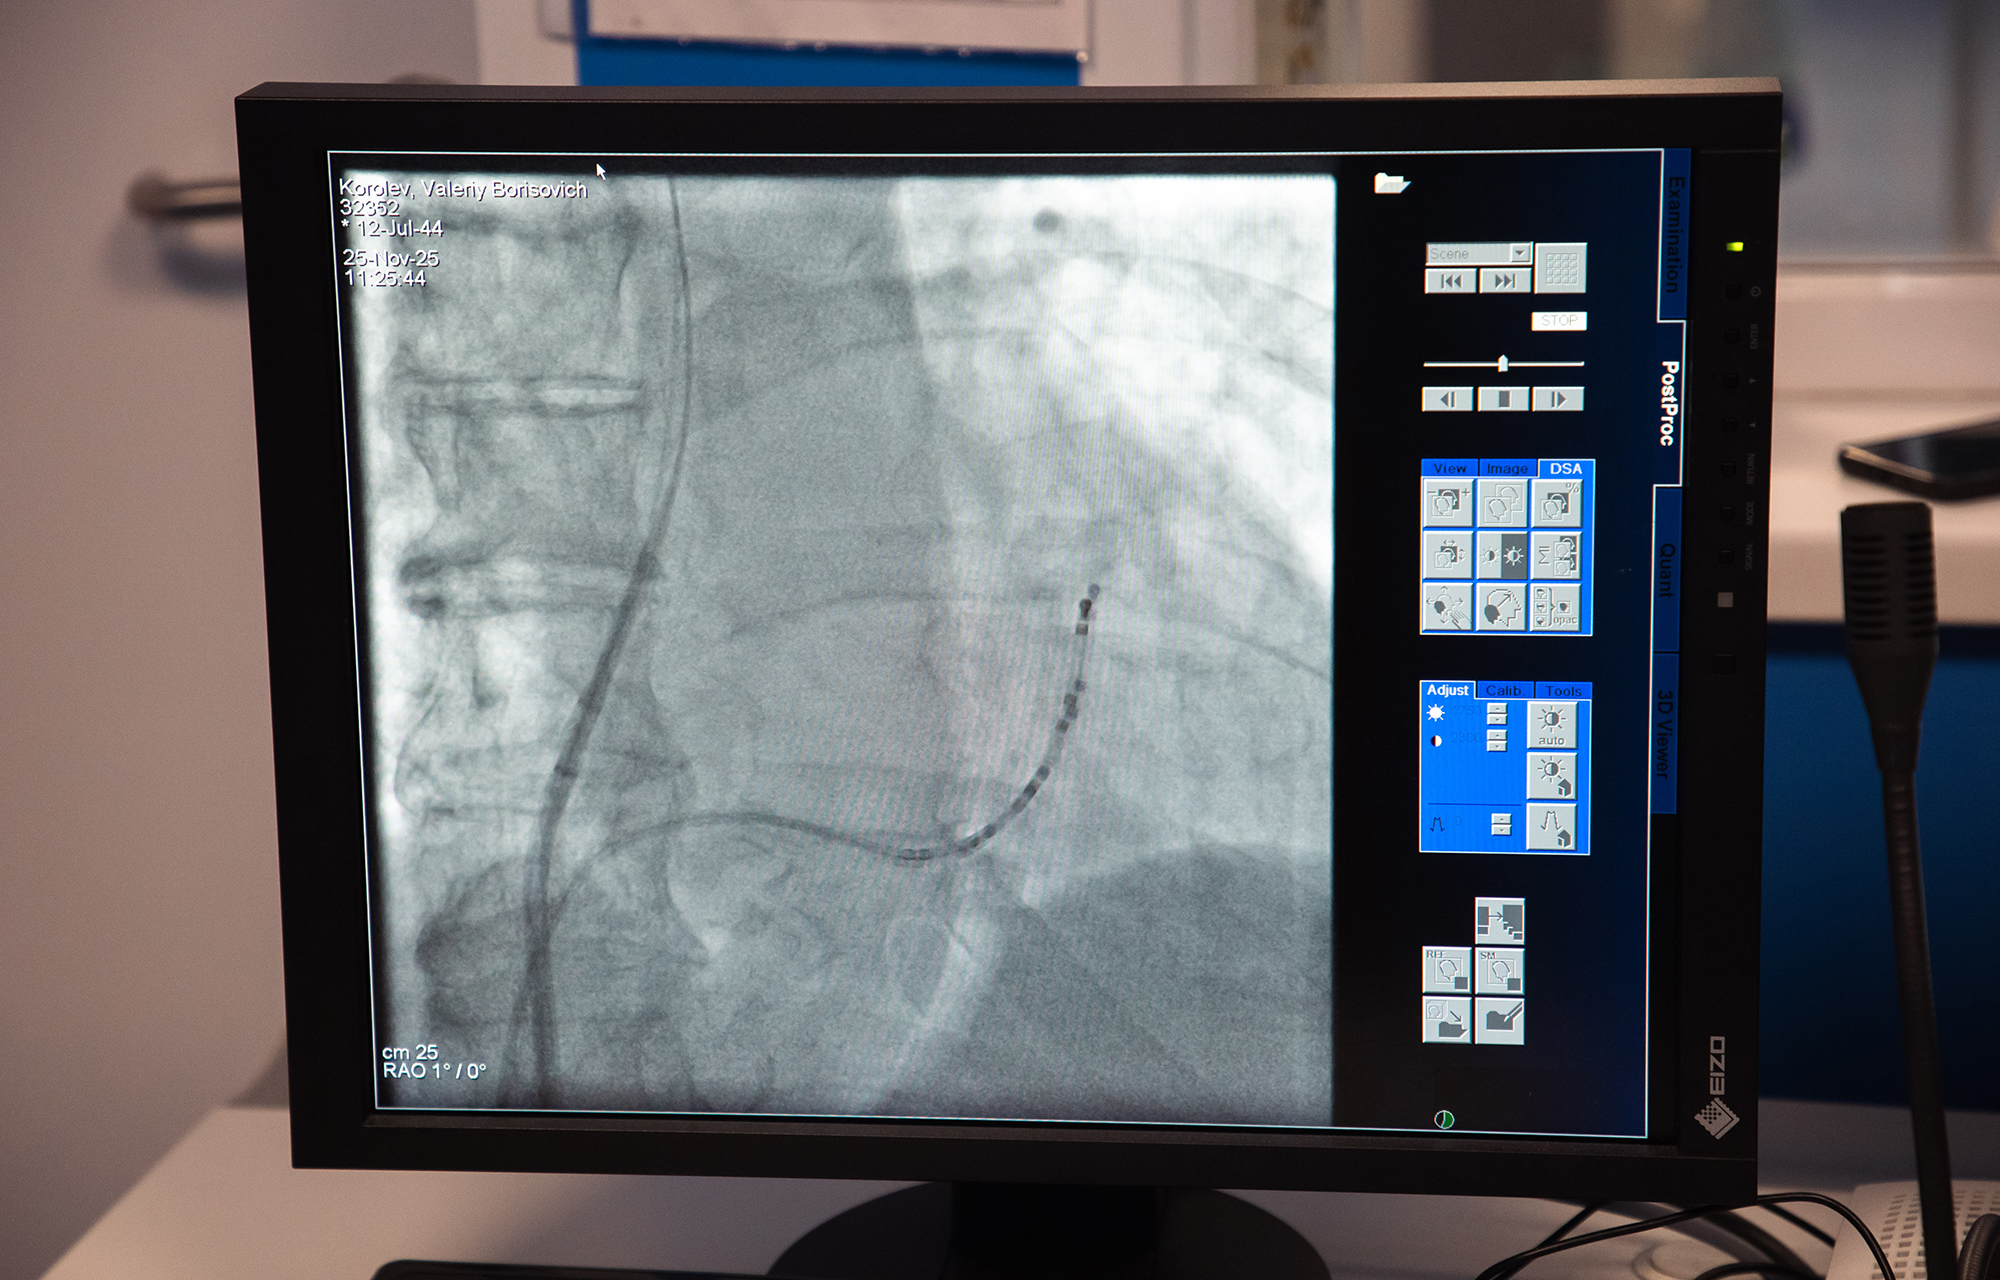

Недавно специалисты внедрили криоаблацию для пациентов с фибрилляцией предсердий (мерцательной аритмией).

«Операция проводится эндоваскулярно, то есть без вскрытия грудной клетки. Используются ангиограф, навигация, современное криооборудование. Специалисты умеют делать операцию на уровне коллег из федеральных клиник».

Криоаблация проводится быстро — операция длится всего 1–1,5 часа, а пациенты уже через несколько дней выписываются домой.